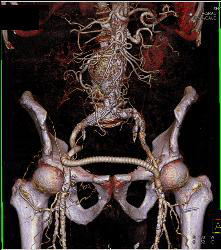

Occluded Left Iliac Artery With A Fem-fem Bypass